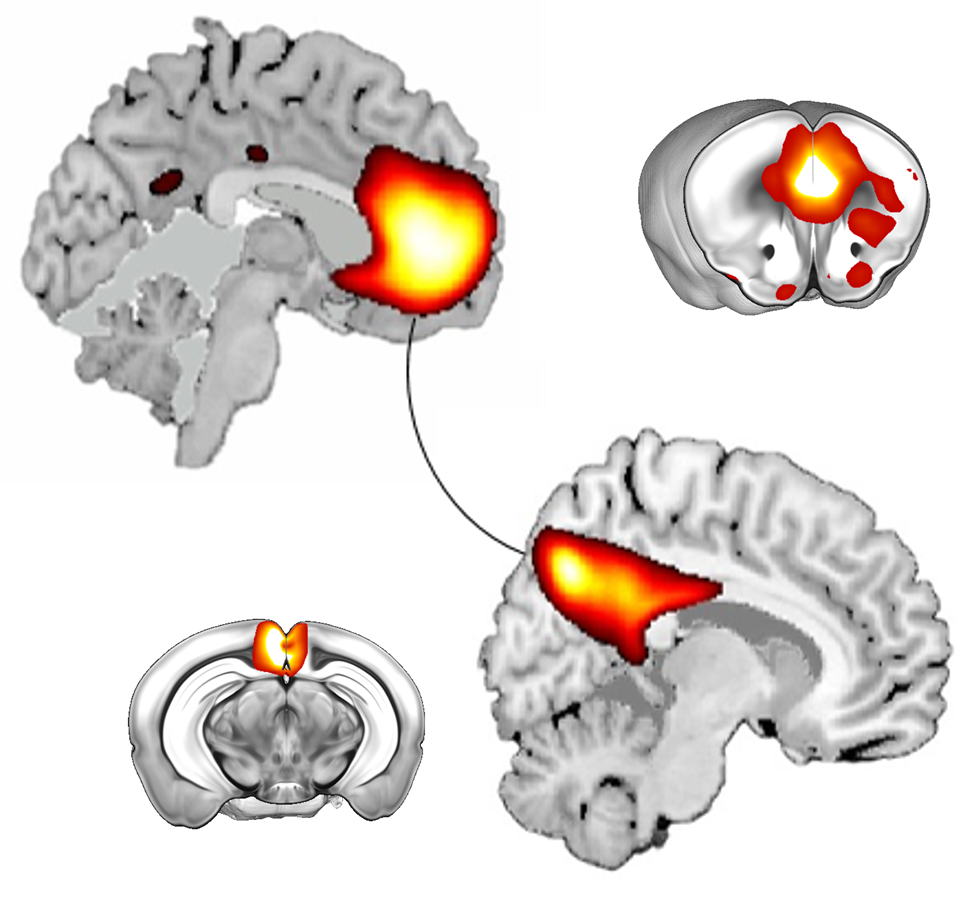

Our aim is to uncover the mechanisms underlying cognitive and social alterations relevant to psychiatric and neurodevelopmental disorders with the final goal of developing biologically-based and personalized therapeutic strategies. We employ cross-disciplinary approaches including detailed in vivo studies in genetically modified mice strictly combined with clinical investigations.